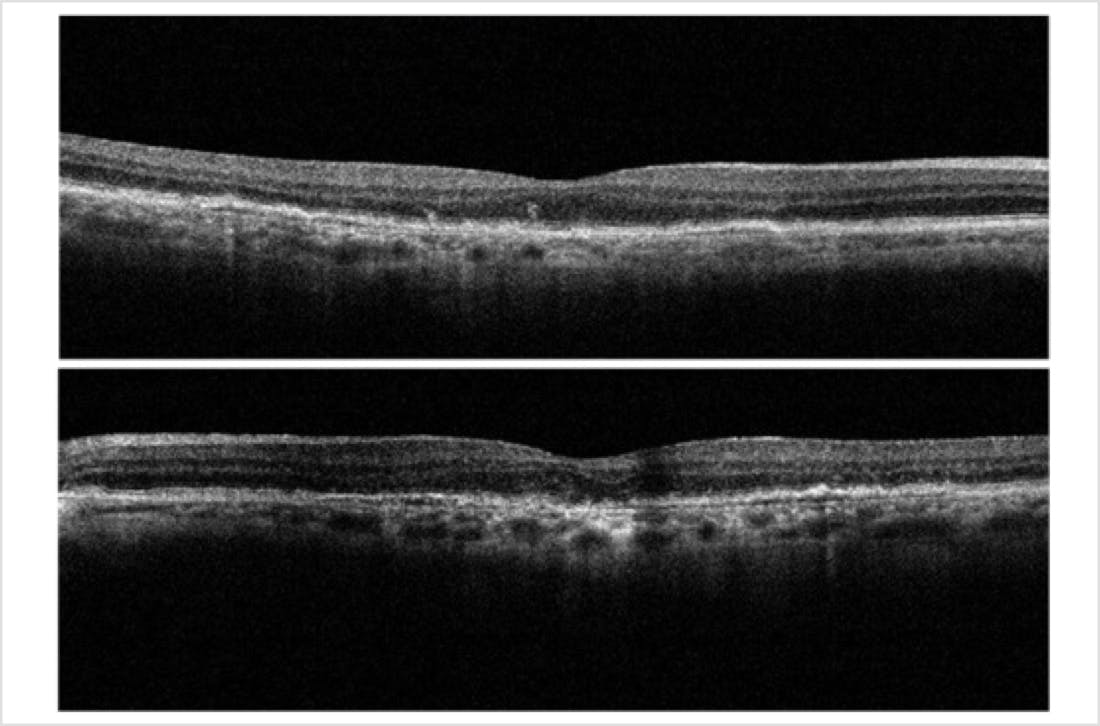

The patient’s BCVA was 20/25 bilaterally. Examination of the anterior segment revealed well centered posterior chamber IOLs with trace posterior capsular fibrosis in both eyes. Ophthalmoscopy revealed medium size drusen, mild RPE changes, and multiple areas of non-central geographic atrophy (GA) in both eyes. Color photography confirmed the clinical findings (Figure 1). Fundus autofluorescence (FAF) demonstrated well demarcated areas of parafoveal hypoautofluorescence consistent with GA. Additionally, these lesions had hyperautofluorescent borders, a known risk factor for progression (Figure 2). Optical coherence tomography (OCT) showed drusen, intraretinal hyperreflective foci, ellipsoid zone attenuation, early choroidal hypertransmission defects, and no evidence of intraretinal or subretinal fluid (Figure 3).

The patient presented back in my clinic approximately 6 months after the initial consultation. He noted persistent symptoms of difficulty with reading and using the computer but denied any significant worsening since the last visit. His BCVA was 20/25 OD and OS. Anterior segment examination revealed well centered posterior chamber IOLs with trace posterior capsular fibrosis in both eyes. His clinical examination was unchanged. Careful review of his retinal imaging revealed progression of the hypoautofluorescent lesions on FAF (Figure 4). OCT revealed worsening choroidal hypertransmission defects OS>OD with no evidence of exudation (Figure 5).

This case is notable for several reasons. First, it shows the utility of multimodal imaging, and in particular, the use of FAF imaging for monitoring patients with GA. Note that in Figure 1, it is difficult to appreciate the borders of the GA lesion, whereas in Figure 2, clearly evident are hypoautofluorescent areas (indicating areas of already dead retinal pigment epithelium) and hyperautofluorescent areas (indicating areas of potential expansion of the GA lesion). Meanwhile, the OCT image in Figure 3 helped support the diagnosis of GA while also demonstrating key signs of potential progression. With the benefit of serial imaging captured at the follow-up visit (Figure 5), it was possible to detect progression of this patient’s GA despite stable visual acuity and no change on clinical examination.